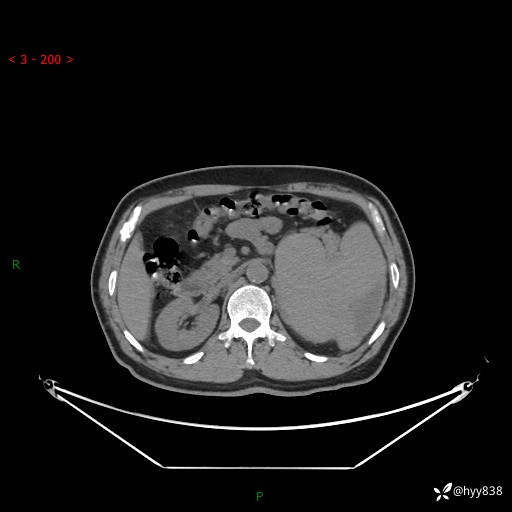

上腹部CT平扫

增强(动脉期+静脉期)